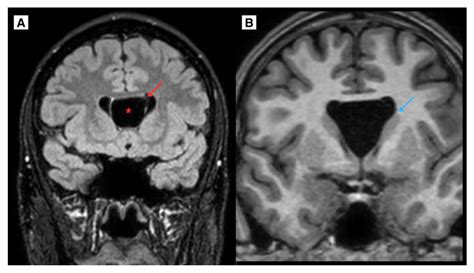

Diagnostic Imaging of the Cavum Septum Pellucidum

Diagnostic imaging techniques, such as magnetic resonance imaging (MRI), are essential for visualizing the Cavum Septum Pellucidum and assessing its size and shape. MRI provides high-resolution images of the brain, allowing clinicians to detect abnormalities in the Cavum Septum Pellucidum and other structures.

MRI is the preferred imaging technique for evaluating the Cavum Septum Pellucidum due to its high resolution and ability to differentiate between soft tissues. CT scans and PET scans may also be used in specific clinical contexts, but they are less commonly employed for assessing the Cavum Septum Pellucidum.